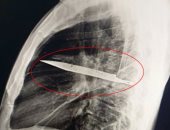

تنزانى يكتشف بالصدفة شفرة سكين دخلت جسمه منذ 8 سنوات بعد ألم فى الصدر

الثلاثاء، 19 أغسطس 2025 10:32 ص

أصيب رجل من تنزانيا بصدمة كبيرة بعدما اكتشف الأطباء أن شفرة سكين ضخمة كانت مستقرة فى صدره منذ 8 سنوات من دون أن يدرك ذلك.